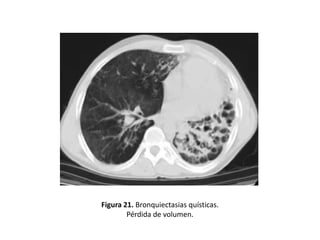

• Otros hallazgos demostrables mediante un estudio

con TAC y que pueden constituir signos indirectos de

BQ serían: (figuras 19-22).

– Enfisema

– Irregularidad de la pared bronquial

– Atelectasias

– Pérdida de volumen o áreas de consolidación

Figura 21. Bronquiectasias quísticas.

Pérdida de volumen.

• Quísticas:

– Es la expresión más grave de la enfermedad.

– Los bronquios adquieren una forma sacular o de

quiste.

– Pueden presentar niveles hidroaéreos o estar

agrupadas en racimos o hileras.

– Adoptan la típica imagen de “nido de golondrina”

cuando el moco se acumula dentro de las lesiones y

aparece un nivel hidroaéreo (Figuras 11, 14, 15, 17, 21

y 25).

– Son frecuentes en la aspergilosis broncopulmonar

alérgica (ABPA) y en la fibrosis quística

• Los distintos tipos morfológicos se correlacionan

con la severidad de la enfermedad (las varicosas y

quísticas son manifestación de una enfermedad

más avanzada).

• Pacientes con BQ quísticas presentaban con más

frecuencia esputos purulentos, colonización por

Pseudomonas aeruginosa y mayor alteración de

los parámetros espirométricos que los pacientes

con BQ cilíndricas o varicosas.